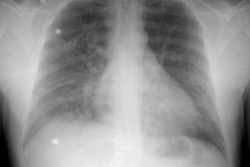

PURPOSE: To evaluate the pulmonary vasculature in patients with hepatopulmonary

syndrome. MATERIALS AND METHODS: Conventional computed tomographic (CT) scans in

eight patients with hepatopulmonary syndrome were retrospectively evaluated to

compare the diameters of the pulmonary trunk, right and left main pulmonary

arteries, and peripheral pulmonary vasculature in the right posterior basal

segment with those in eight healthy subjects and in four patients with

normoxemic cirrhosis. With thin-section CT, the ratio of segmental arterial

diameter to adjacent bronchial diameter in the right lower lobe in four patients

with hepatopulmonary syndrome was compared with that in four patients with

normoxemic cirrhosis. RESULTS: In patients with hepatopulmonary syndrome, the

peripheral pulmonary vasculature was significantly dilated compared with that in

control subjects and in patients with normoxemic cirrhosis (P = .002); however,

the central pulmonary arteries were not significantly dilated (P > .05). At

thin-section CT, the ratio of segmental arterial diameter to adjacent bronchial

diameter was significantly greater than that in patients with normoxemic

cirrhosis (P < .05). CONCLUSION: In patients with hepatopulmonary syndrome,

the peripheral pulmonary vasculature is significantly dilated. Dilatation of the

peripheral pulmonary vasculature may be helpful in the diagnosis of

hepatopulmonary syndrome.